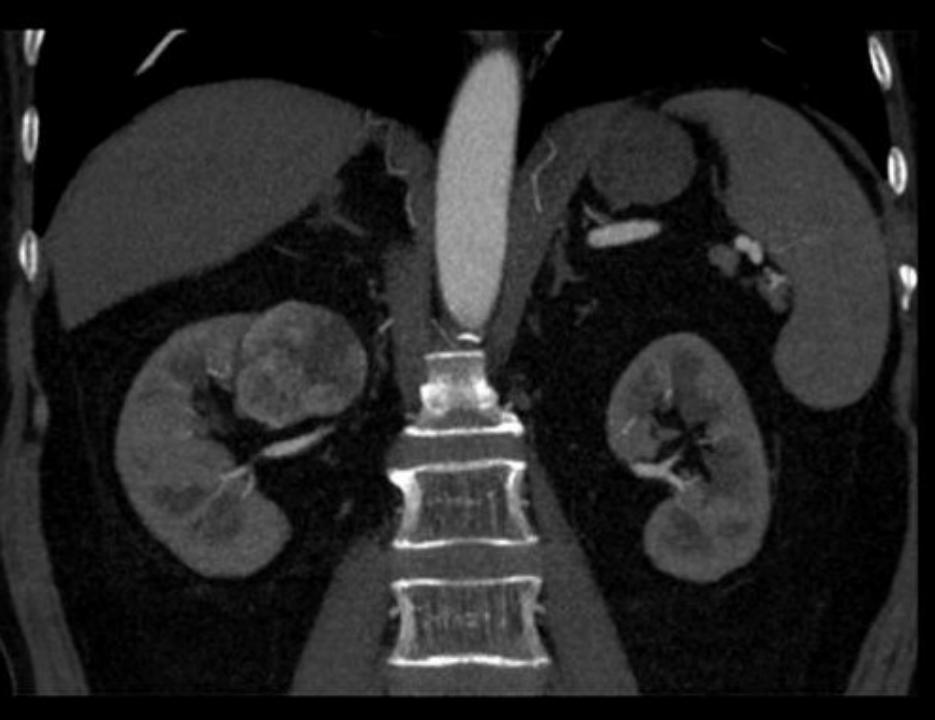

肾动脉CTA:右肾占位,大小约4.7*4.5cm,类圆形低密度影,增强扫描呈不均匀强化,考虑恶性;右肾动脉分支供血。

患者老年男性,体检发现右肾占位,肿瘤最大径约4.7cm,影像资料显示肿瘤位于右肾背侧上极,紧贴肾门处,底部一支肾脏动脉分支环绕。这个位置对于保肾手术来说是一个极其不利的位置,经腹腔或经后腹腔途径来游离暴露肿瘤都不会太方便,肿瘤几乎位于视野的盲区,难以得到充分的操作空间。患者基础疾病多,为保肾慕名而来,任善成主任评估患者病情,制定手术方案:机器人辅助腹腔镜经腹右肾部分切除术。

2.暴露肿瘤:肿瘤的位置位于上极背侧,紧贴肾门上缘,在游离肾周脂肪时发现整个肾周脂肪灶化特别严重,脂肪紧紧黏贴肾包膜,强行游离会损伤肾包膜引起出血。因此术中在将肾肿瘤的大致轮廓游离出后,并未强行去寻找肿瘤的明确边界,以防止损伤包膜出血。